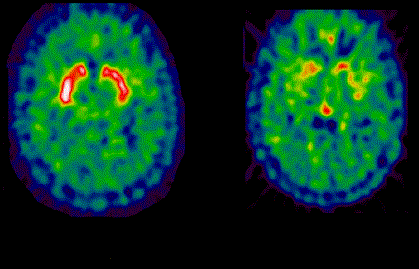

The Parkinson’s disease (PD) pipeline currently has 302 products in active development across all stages, but a stark contrast between the mechanisms of action employed in the current market and the pipeline is evident. Where the market relies on symptomatic treatments that target neuromodulatory receptors, the pipeline shows a diverse range of neuroprotective therapies targeting dysfunctional disease processes. This diversity is partially due to the presence of 90 first-in-class products, which accounts for 37% of the overall pipeline therapies that disclosed their target. In an industry, market and development landscape that favors first-in-class over non-first-in-class development in many ways, such as through faster approval or greater revenue, this finding has strategic implications for a wide array of market participants, both large and small. Despite their historically high attrition rate, first-in-class therapies that reach the market have the potential to transform and improve the PD treatment landscape.

PD is a complex and multifaceted disease with a complex interplay between different pathological processes. Enormous research efforts and significant technological advances have furthered knowledge of the neuroanatomy of the basal ganglia and of the fundamental processes underlying neurodegeneration, helped by the ongoing identification of susceptibility genes and causative genes in familial PD. Although the exact mechanisms that initiate onset remain unclear, these insights have been translated into the pool of novel therapeutic targets, which may potentially become disease-modifying therapies by aligning to the disease processes and some genetic determinants of PD.

GBI Research’s proprietary analysis showed substantial variation in how well the functional roles of PD first-in-class targets align to the parkinson's disease pathophysiology. Further in-depth analysis identified the most promising first-in-class targets based on various scientific and clinical parameters. Examining scientific and clinical data of promising first-in-class targets showed that first-in-class status is not, in its own right, enough for a successful product; however, the first-in-class products substantiated by scientific and clinical evidence will be exciting future prospects with the potential to transform the global parkinson's disease market.